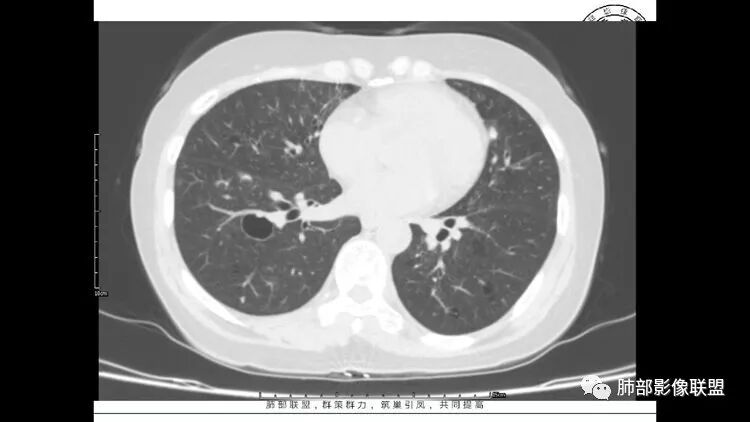

患者中年女性,因右眼红痛1天就诊。胸CT:双肺多发囊性变及结节影,囊以中下肺为多,部分囊内可见分隔及肺动脉,结节部分为实性,部分为混合性,边缘光滑,未见明显毛刺、棘突、胸膜牵拉及血管集束征象。双中下可见支气管扩张及树丫征。淋巴结无明显肿大。综合考虑:一元淋巴细胞间质性肺炎。多元鉴别肺腺癌并转移等恶性病变。

中年女性,因“角膜炎”入院,自用眼液2年,(眼干?)肺部:双肺多发类圆形薄壁气囊+实性结节+GGO,下肺分布为主,纵隔淋巴结肿大,考虑淋巴系统增殖,LIP可能性大,可能继发于干燥综合症;左肺下叶的混合磨玻璃结节形迹可疑,边界清晰,内部疑似空泡,扩张扭曲支气管,极像肺癌,伴双肺转移?待排吧